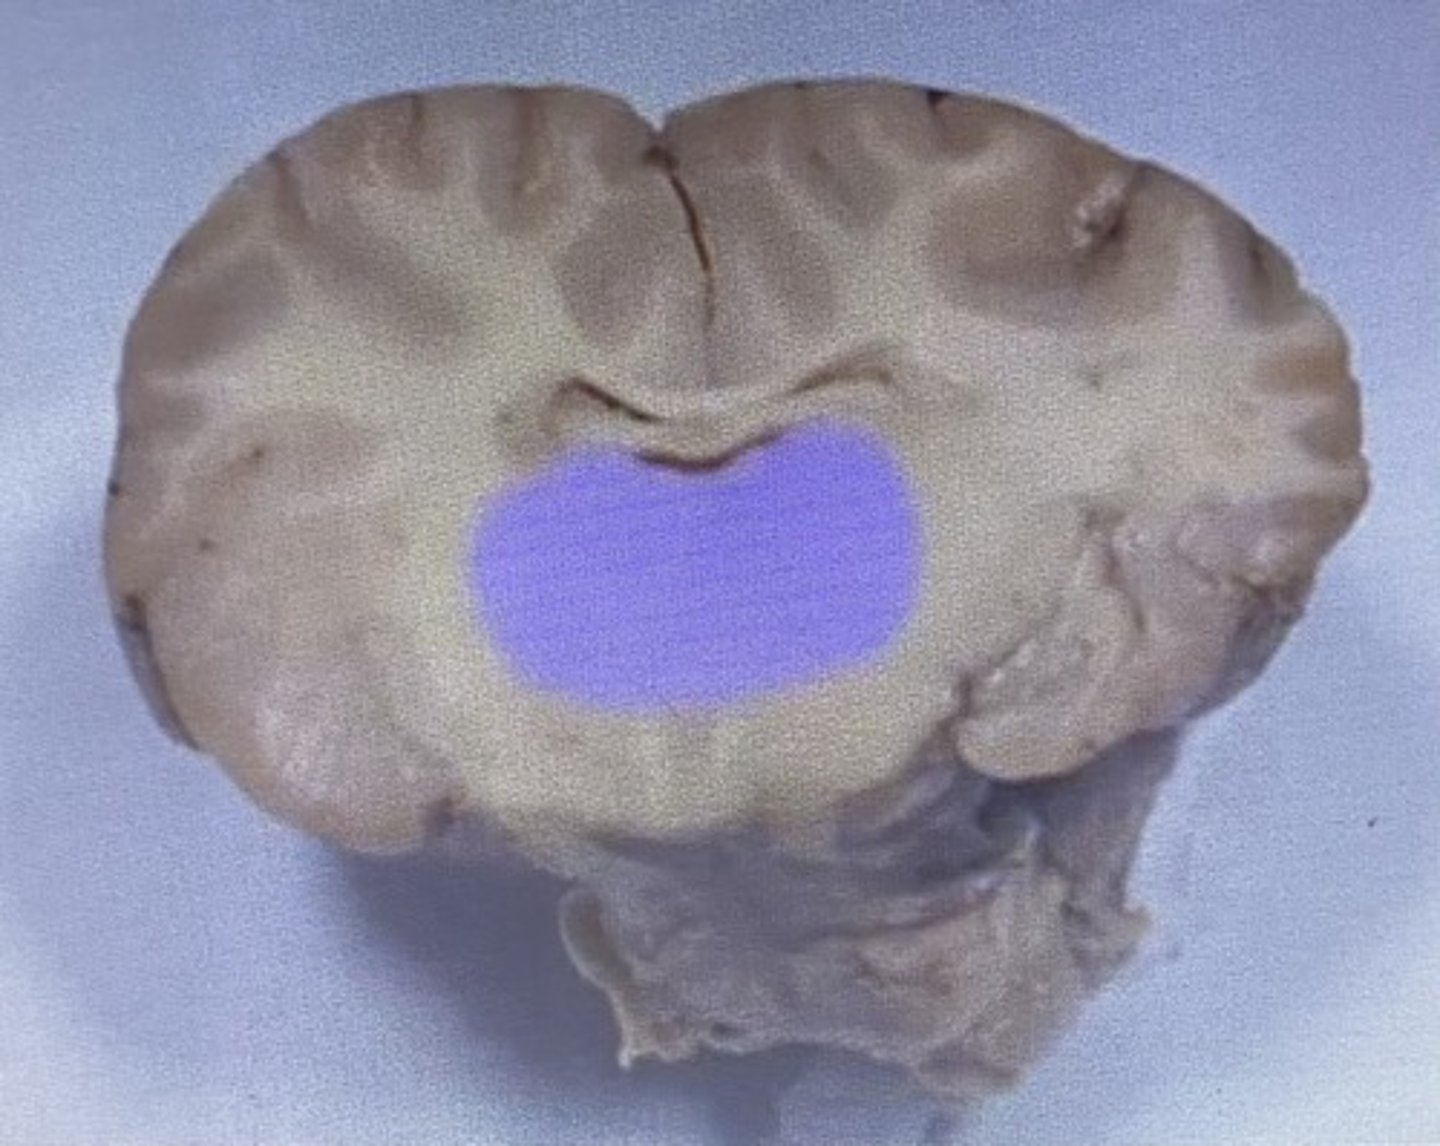

Sheep Thalamus

-gateway to cerebral cortex

Thalamus

Sheep Third Ventricle